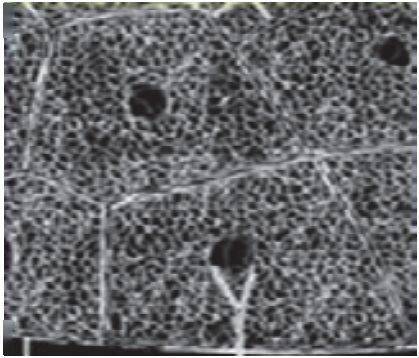

在磨玻璃病灶内部常可见细网格状阴影,类似铺路石状,称为细网格征或铺路石征(图 2-4)

提示病理改变为小叶间隔及小叶内间隔增厚,反映间质性病变,也有的学者解析为血管网增多,符合肺部病毒感染病理特性

图 2-4 细网格征或铺路石征 (共4张)